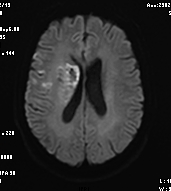

2月16日,72岁的黄先生在家中突发左侧肢体无力伴言语不清,家属将其送至我院急诊科就诊,卒中团队会诊后考虑急性脑卒中,NIHSS评分:20分,并立即护送患者至放射科。放射科医技护启动绿色通道,在3分钟内完成一站式卒中CT检查,并对脑CT灌注(CTP)及CT血管造影(CTA)图像进行快速评估:可见患者双侧颈内动脉及右侧大脑中动脉均闭塞(图1);CTP显示患者右侧大脑半球血流灌注减低(图2),但存在较大面积的缺血半暗带(图3),这提示如果能及时改善血运,可挽救大部分缺血脑组织,显著缩小脑梗死的范围,进而改善患者预后。基于可靠的影像证据,神经内科卒中团队当机立断通过急诊介入手术成功取栓并扩张颈内动脉,患者右侧大脑半球及时恢复了血供。术后第2天患者四肢、言语功能恢复良好,NIHSS评分:7分。术后第3天后MRI复查显示脑梗死范围远远小于术前低灌注区域(图4)。

图4:术后第三天MRI复查显示脑梗死范围明显小于术前低灌注面积